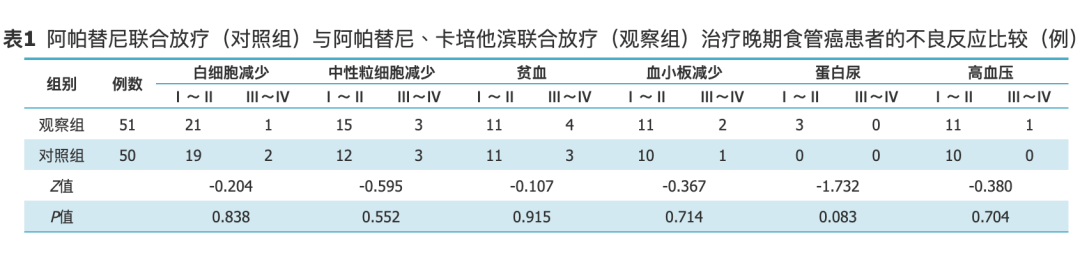

前言食管癌是临床常见消化道恶性肿瘤之一,在我国的发病率位于第6位,死亡率位于第4位[1,2]。食管癌早期症状不典型,因此在确诊时大部分患者已为晚期,错过了最佳手术...

食管胃结合部癌是发生在食管与胃的移行带的肿瘤,其发病率呈逐年上升趋势。大部分病人在就诊时已处于晚期,失去手术机会。目前,晚期食管胃结合部癌没有最佳的治疗方式,经放...